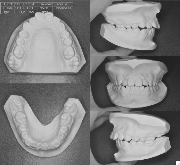

ステップ5.精密検査

口腔内写真,レントゲン

(必要に応じてCT)

印象(歯型)採得

装置装着前

装置装着後